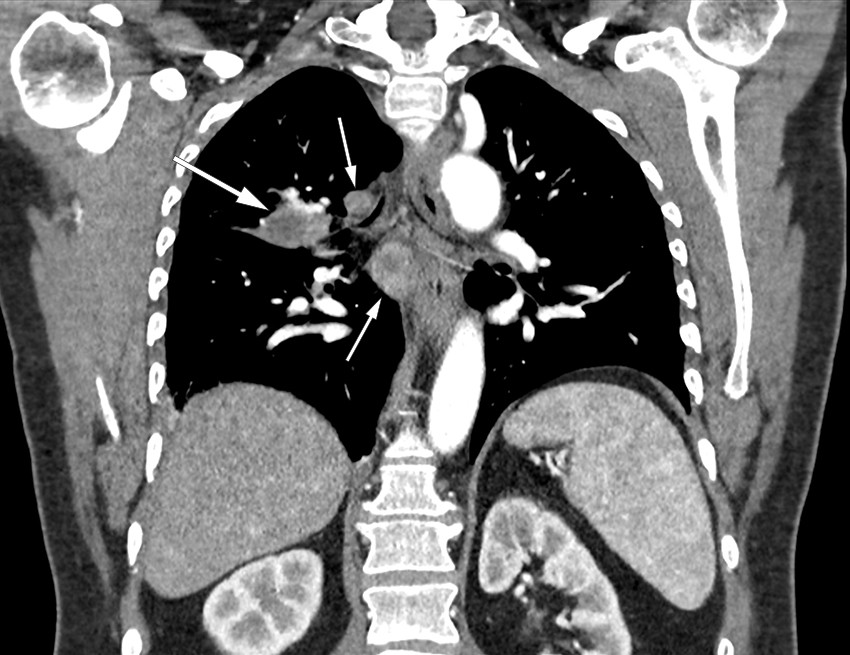

Previous pneumonia was considered a possible diagnosis. However, on account of the persistent night sweats, the general practitioner referred the patient for a CT scan of the thorax and abdomen. The images showed significant mediastinal lymphadenopathy and two consolidations in the right lung. The lung masses and lymph nodes both showed signs of central necrosis (Figure 1). The findings were described as suspicious of malignancy, with enlarged adrenal glands suggesting possible adrenal metastases. The patient was therefore referred to the local hospital on the lung cancer pathway.

On chest X-ray, pulmonary tularaemia typically manifests as opacities and hilar lymphadenopathy. CT thorax generally reveals enlarged lymph nodes and multiple consolidated, nodular opacities, often in the periphery. A characteristic sign of the disease is the presence of central necrosis in lymph nodes and opacities, as was seen in our patient (4, 6, 9). The difficulty of distinguishing pulmonary tularaemia from malignancy, particularly lung cancer, is recognised in the literature (4, 5, 7). It is therefore important that radiologists are informed of any clinical signs of infection.